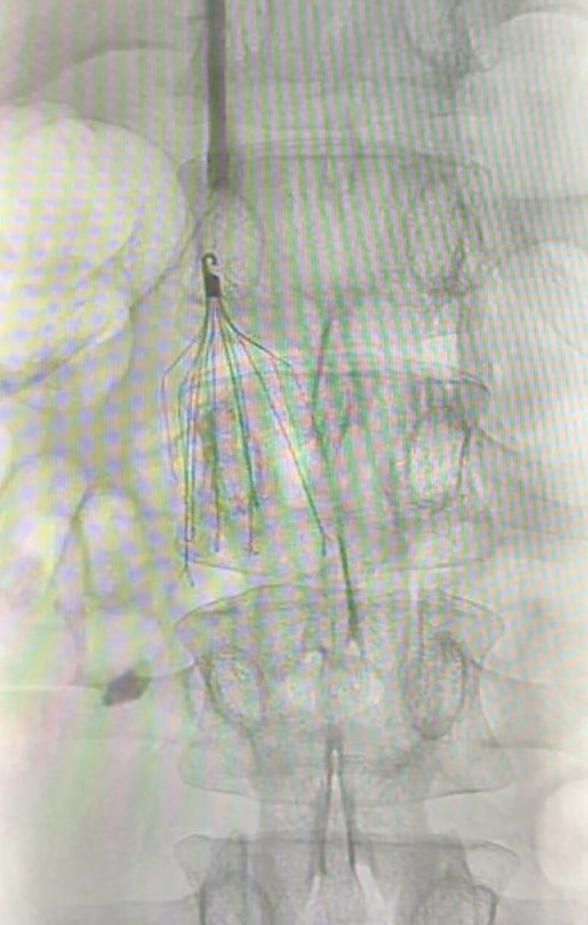

Prior to surgery, urgent placement of a right percutaneous nephrostomy was requested to preserve right renal unit function, given the entrapment caused by the retroperitoneal mass as demonstrated on CT and on the 3D reconstruction (Figure 1).

A CT angiography (CTA) was also requested to assess vascular relationships and enable three-dimensional reconstruction using the Cella system. Additionally, an inferior vena cava (IVC) filter was placed via right jugular vein access at the L1 level (left juxtarenal position), as there was no available space below the renal vasculature. This was performed to allow safe discontinuation of anticoagulation prior to surgery (Figure 2).